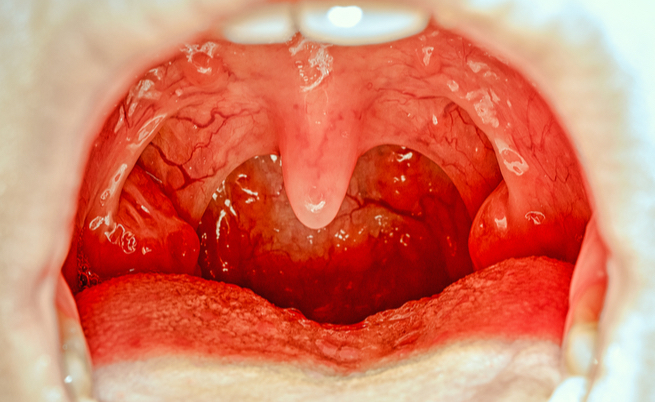

È capitato a tutti di avvertire una sensazione di palato gonfio, spesso accompagnato da prurito, che si estende a tutta la parte interna della bocca. Sovente si tratta di un fastidio temporaneo, della durata di qualche minuto, altre volte invece il prurito e il gonfiore potrebbero essere persistenti.

In questi casi, non è da escludere la presenza di un’infiammazione più o meno grave. Vediamo insieme cosa fare per il palato gonfio, insieme alle cause che potrebbero determinare questa condizione.

Definire la causa esatta che determina una condizione di palato gonfio non è semplice. Spesso, infatti, è determinato da una serie di fattori di varia gravosità.

Oltre all’ustione accidentale, che è la causa più frequente che determina prurito al palato, dovuta all’ingestione di liquidi o cibi troppo caldi, vi sono altri fattori che potrebbero determinare gonfiore e infiammazione. Tra questi, ricordiamo: